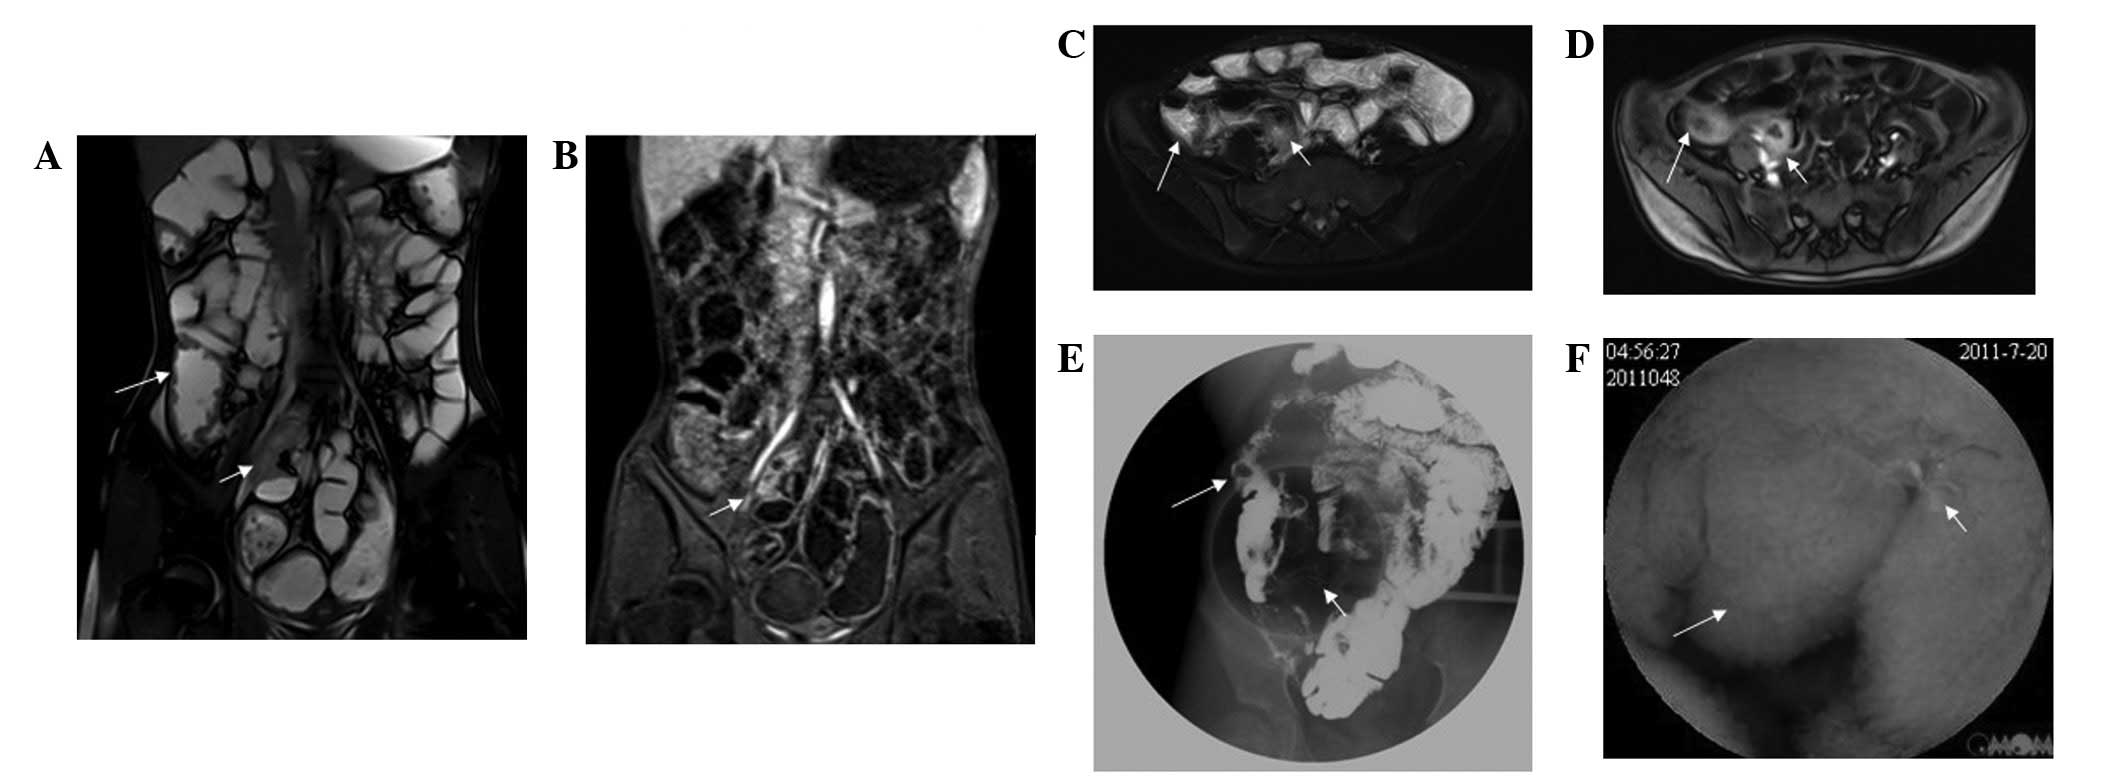

MRI clearly shows all cases with bowel disease. Among the 55 cases, 37 cases involved the small intestine (distal ileum) while 49 cases involved the colon, including the sigmoid colon, rectum, descending colon and ascending colon. An inflamed bowel was observed in a number of cases, with an average of 2.7 lesions per case. In these cases, enhanced MRI demonstrated a significantly augmented intestinal wall with an increased thickness of 5–14 mm. The majority of the lesions thickened circularly and unevenly, which narrowed the lumen (Fig. 1). Cellulitis or inflammatory masses were formed around the bowel presenting related mesenteric fat hyperplasia, fibrosis, thickening, short T1 high signal and significantly widened intestinal clearance (Figs. 2 and 3). Mesenteric lymph node enlargement and retroperitoneal lymph node enlargement were observed in three patients, while six cases presented ascites. Fistulae were not observed between the small intestine and colon; however, four cases with abdominal wall fistula and two cases with anal fistula were observed.